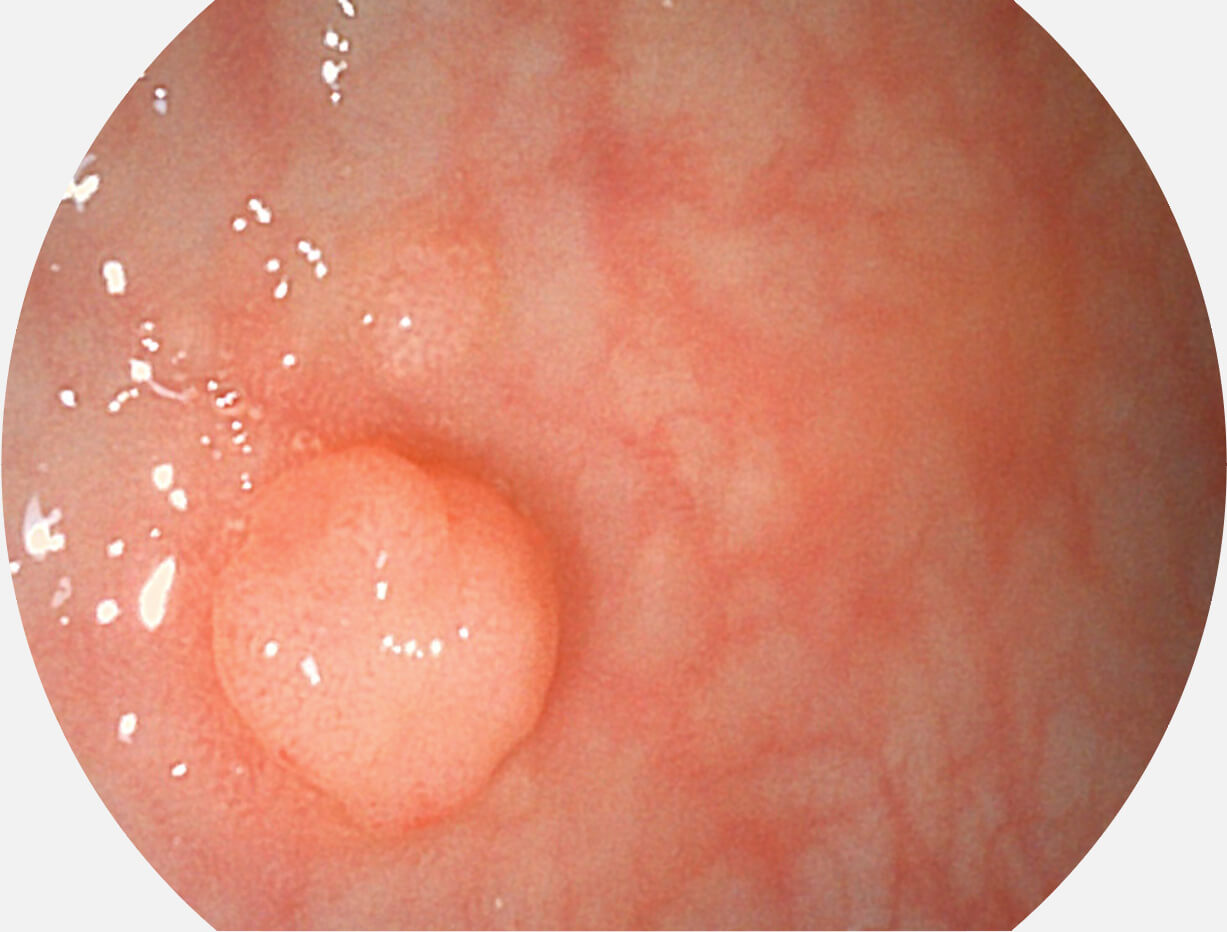

图像具有高亮度、高黏膜血管颜色对比度的特点,且不改变粘液、食物残渣、粪便的基本颜色,可在中远景下进行观察,助力消化道早期疾病的诊断。

SFI图像